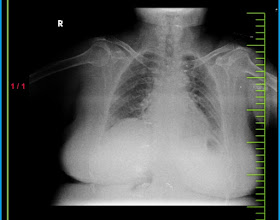

PPM 1 - Can you use your medical expertise to diagnose this x-ray? Also @PPM6.

PPM 1 - πStart counting the vertebrae from L5 which is just above the sacrum and then see the size of each vertebrae till you reach L2 and L1.

PPM 4 - Spondylolisthesis?

PPM 6 - Lumbar Spondylosis with Intervertebral Disc Degeneration.

lumbosacral region of the spine, which includes the lumbar vertebrae (L1 to L5) and potentially part of the sacrum (S1). This area supports much of the upper body's weight and is a common site for degenerative changes like disc degeneration and spondylosis.

PPM 7 - Collapsed vertebra.

Why don't you look carefully at the size of each lumbar vertebrae?

PPM 1 -No few days, Look carefully at the size of each lumbar vertebrae.

PPM 4 - Reduced size of lumbar vertebrae.

PPM 8 - Osteoporosis?

PPM 4 - Osteoporosis, Degenerative Disc Disease, Vertebral Compression Fractures, Aging. (Differentials from cgpt. I needed to take help)

For this patiet can rule out aging, can rule in possible influence of hormones causing osteoporosis.

Degenerative Disc Disease - unable to identify any reduction in space between vertebrae. Probably rule out.

Collapsed / fractured because of osteoporosis.

PPM 1 - Yes vertebral fractures present as a wedge shaped collapse.

PPM 9 - But this is osteoporosis most probably.

PPM 1 - Even the size of the second and third appears reduced.